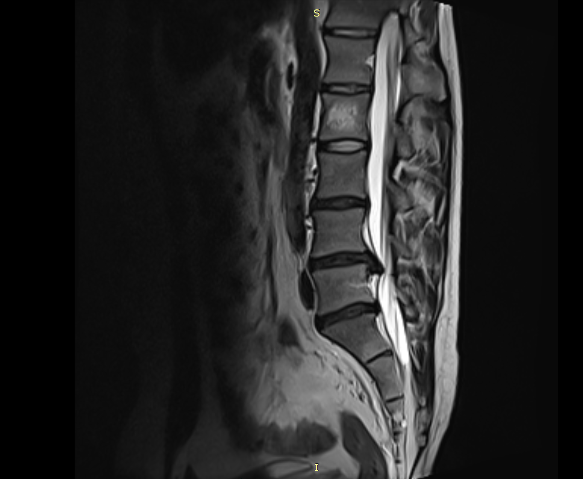

Kan testleri( özellikle romatizmal iltihabi durumlarda) ve başlangıçta basit filmler ve daha sonra detaylı MR ve dizilim grafileri gibi ( ortoröntgenogram ) görüntüleme yöntemlerine dayanır.

Radyolojik muayeneler

Fizik muayene dizde kireçlenme olabileceğini gösteriyorsa, tanıyı doğrulamak ve diğer rahatsızlıkları ekarte için görüntüleme testleri gerekir.

Röntgenler, ileri evre diz osteoartriti teşhisinde çok faydalıdır çünkü eklemin kendine özgü özellikleri vardır, bunlar arasında şunlar bulunur:

Kemikler arasındaki eklem boşluğunun azalması: Kıkırdak aşındıkça, aralarındaki eklem boşluğu genellikle daralır.

Kistler: Vücut kıkırdak yıkımına tepki verirken ve eklemi stabilize etmeye çalışırken, kemikte kistler veya sıvı dolu boşluklar oluşabilir. Artan kemik yoğunluğu ve eklem yüzeylerinde düzensizlik: Kemikler artık kıkırdak tarafından desteklenmediğinde, birbiri içine geçecek sürtünme yaratacaktır. Vücut, buna karşılık daha fazla kemik dokusu üreterek yanıt verecek, bu da kemik yoğunluğunu arttıracaktır. Bu kemiklerde nerdeyse mermer sertliğinde esnek olmayan bir yapıya neden olur. Artan kemik dokusu, aynı zamanda eklem yüzeylerinde düzensizliklere ve eklemde ağrılı kemik çıkıntılarına oluşmasına yol açar.